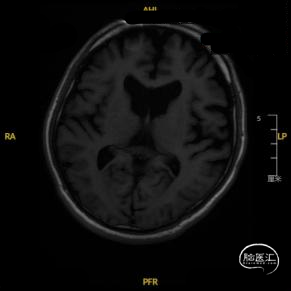

➢ 入院后头核磁检查

患者主因言语不利3天入院,头核磁提示右侧额、顶叶多发低灌注梗塞,脑血管造影提示右侧颈内动脉开口重度狭窄,为责任血管,另外患者前交通动脉、右侧后交通动脉开放不良,并且狭窄严重,考虑到高灌注风险,决定分期处理,一期小球囊扩张改善供血,二期支架成型。